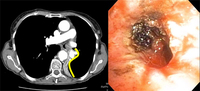

Golden-S or reverse S-sign on chest CT (left image) traced by yellow line. Flexible bronchoscopy (right image) shows the central obstructive lesion at the left mainstem bronchi.

From the collections of Jose Fernando Santacruz MD, FCCP, DAABIP and Erik Folch MD, MSc; used with permission